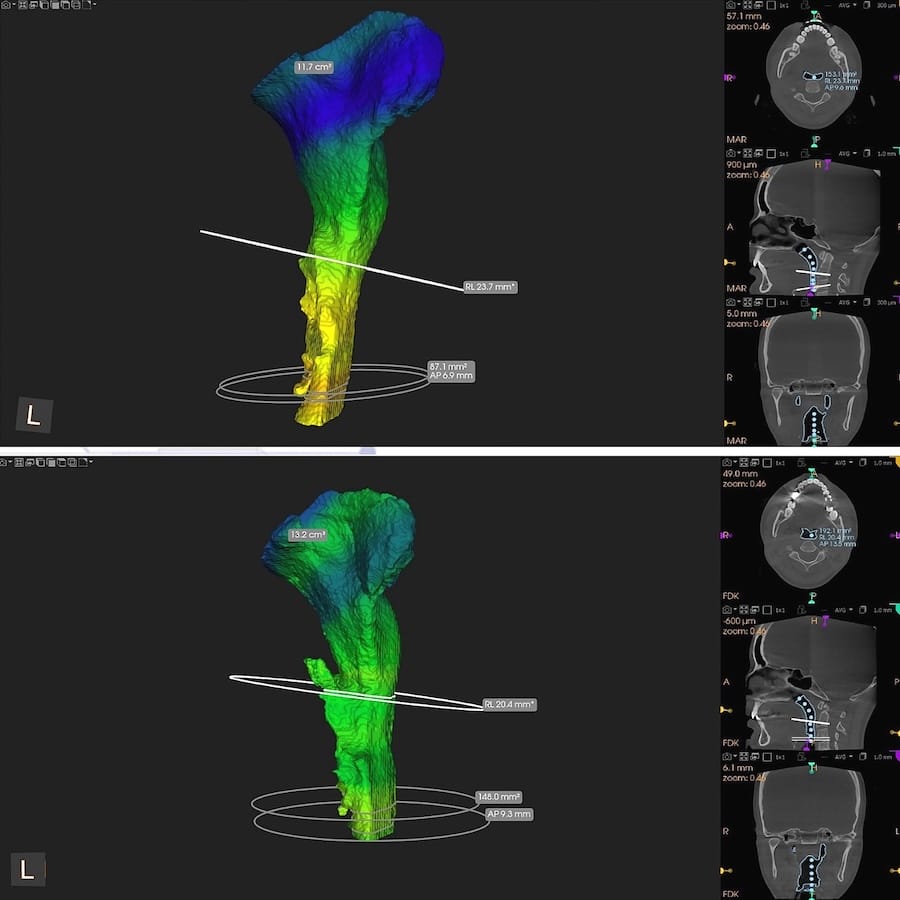

This same physiological response of changing the Disclusion Time from long to short can widen the airway constriction of a sleep apnea patient who wears a nighttime sleep appliance that forces his jaws apart, attempting to open his airway (Figures 13 and 14).11

Figure 13 – A CBCT comparison of airway volumes pre (top pane) to post Disclusion Time Reduction (bottom pane). A much wider airway followed the DTR-induced pharyngeal muscle relaxation (pre DTR Volume = 100.5 mm2; post DTR volume = 157.1 mm2). Note the post DTR airway is more parallel walled without being conically constricted pre-treatment.

Figure 14 – The airway constrictions compared pre (top pane) to post DTR (bottom pane) illustrate the patient’s airway widened following DTR. By gaining 57 mm2 of airway volume, this patient no longer needed his sleep appliance, slept more soundly, and experienced less apneic episodes.